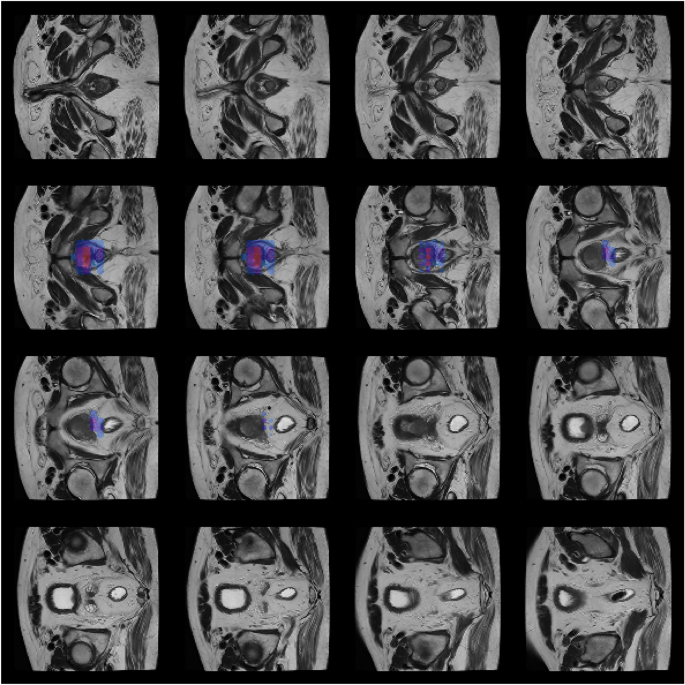

Occlusion Sensitivity involves systematically occluding parts of the input image and observing the changes in the model’s prediction confidence. By sliding a small occluding patch across different regions of the image, we can generate a sensitivity map that highlights the areas most critical for the model’s decision17. In the context of prostate cancer detection, this technique is particularly effective for zonal localization. As the occlusion patch is larger than typical textural features, this method indicates the general anatomical region or slice stack that drives the classification, rather than delineating pixel-perfect boundaries. Figure 3 illustrates this zonal focus, where the model’s confidence drops significantly when the prostate region is occluded.

Occlusion Sensitivity maps for the BIMCV dataset. The heatmaps demonstrate the model’s zonal focus on the prostate gland. The red/blue overlays correspond to regions where occlusion causes the most significant drop in prediction confidence, aligning with the anatomical location of the prostate.